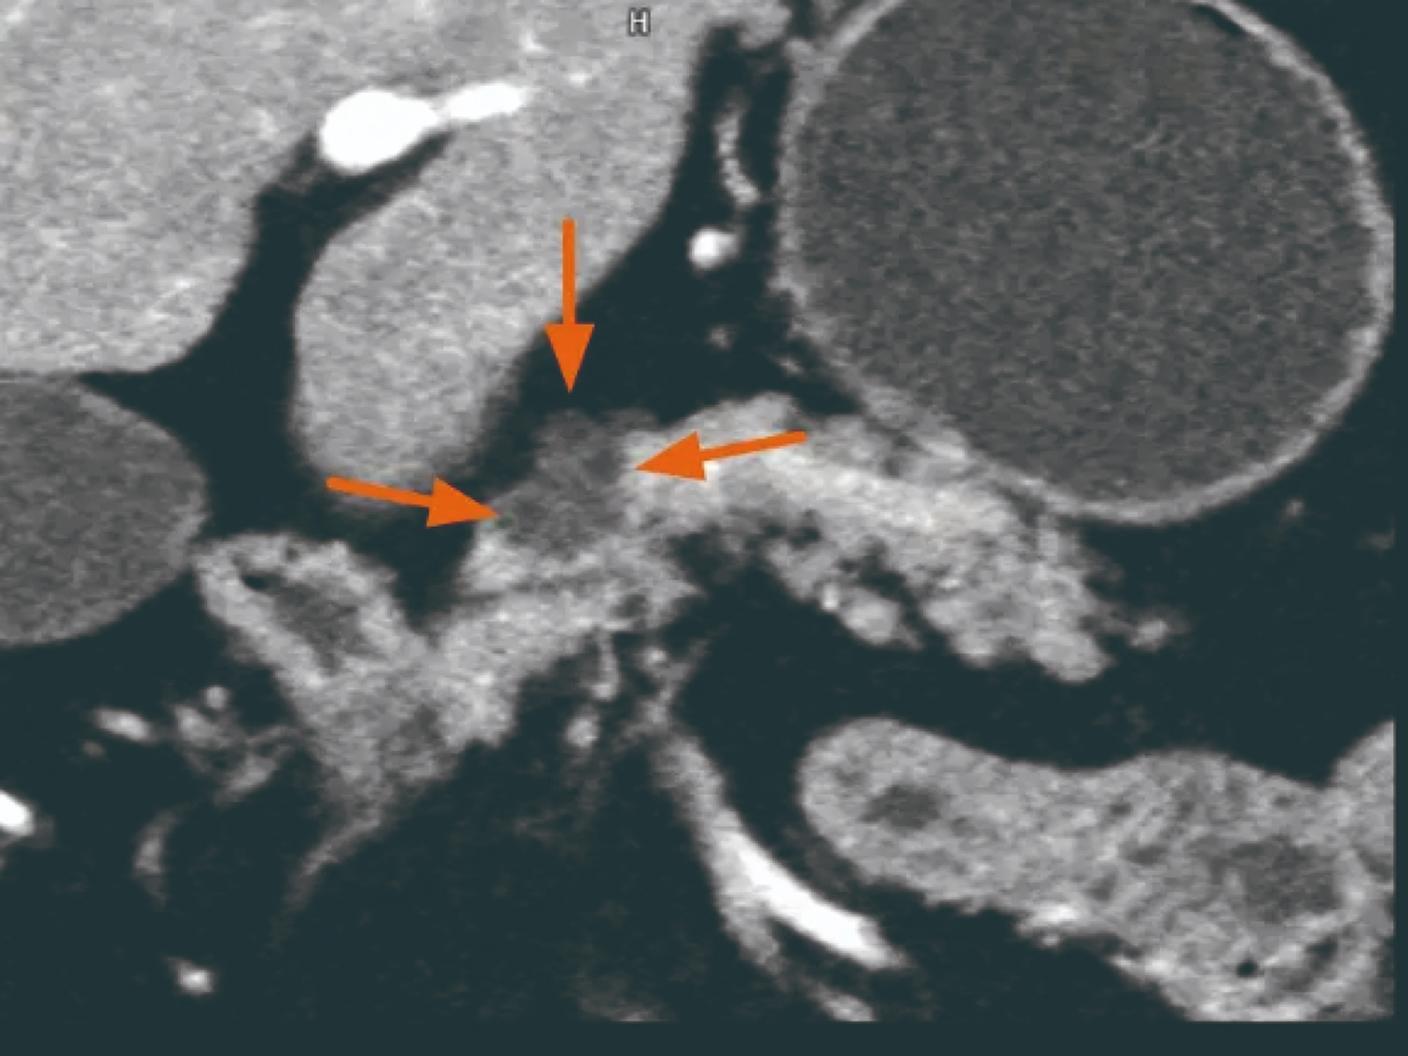

「NAEOTOM Alpha.Peak」および「NAEOTOM Alpha.Pro」が持つ高い時間分解能は、血管系の描出、動脈瘤の詳細な解析、動脈解離の評価などにおいて高い評価をいただいているだけでなく、特に高度石灰化冠動脈を有する心疾患患者さんの診断・治療において、侵襲的なカテーテル検査に代わるものとして、患者さんの身体的負荷軽減や、診断から治療までに要する時間の軽減への貢献が期待されています*4 。